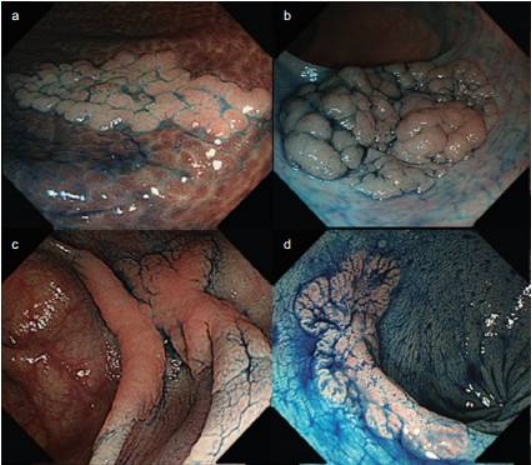

结直肠侧向发育型肿瘤是指直径超过1厘米,沿着大肠黏膜表面侧向生长的平坦或隆起病变,颜色和周围黏膜几乎一致,只要披上肠道粘液,就几乎与肠壁“融为一体”。但它的危害性还特别大,比常见的腺瘤性息肉恶变潜能更高,所以一定要早发现、早治疗。

手术当天,林剑兴主任邀请莆田学院附属医院卢志忠医生联合操作,在内镜下精准探查完整剥离肿瘤,切除范围达5cm×6cm,手术全程顺利。术后病理显示,该肿瘤为直肠原位癌,无明确浸润性病变,经微创治疗实现根治,许奶奶术后安返病房,顺利出院。